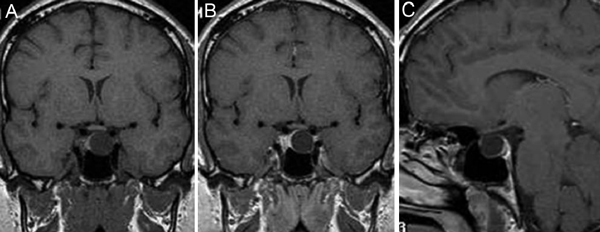

Figura 10A y B. Microadenoma pituitario (prolactinoma), secuencias T1W antes y después de contraste, cortes coronales. Sin Gadolinio el tumor tiene señal similar a la glándula pituitaria. La secuencia T1W post Gadolinio, muestra la glándula contrastada y a izquierda un tumor no contrastado, (hipointenso) de 7 mm (punta de flecha). Características de la imagen del adenoma pituitario

En el caso de los microadenomas, al ser tumores funcionantes, el cuadro clínico y de laboratorio ayuda a definir la localización de la lesión. La glándula pituitaria, considerando el pequeño tamaño de los tumores, puede mostrar forma y volumen normal. En un 20-25% de los casos no se logra demostrar los microadenomas menores de 3 mm, lo que aumenta al 40% en el casos de los adenomas productores de ACTH, en que los exámenes falsos negativos son más frecuentes36-38 (Figuras 11A, 11B, 11C y11D). En este grupo de pacientes es fundamental la utilización de protocolos de examen que incluyan cortes finos coronales de 1 mm en secuencias ponderadas en T1 antes, durante y después de la inyección de Gadolinio, para asegurar la detección de los adenomas, los cuales se contrastan en general más tardíamente que la glándula normal39-41 (Figuras 12A y 12B).